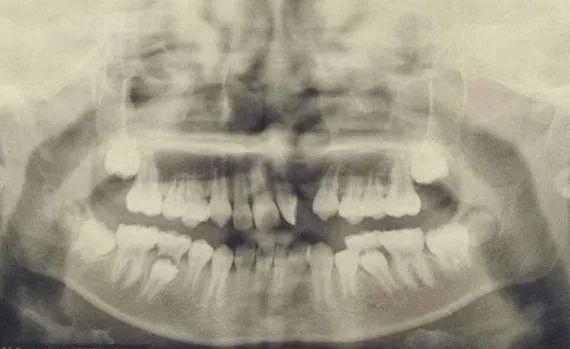

1、術(shù)前需要完善上頜骨全景片或上頜骨CT,了解上頜骨骨質(zhì)缺損情況,可提前預(yù)估手術(shù)難易及髂骨采取量。

齒槽突裂與腭裂的發(fā)病機(jī)理相同,它的發(fā)生是在胚胎發(fā)育期由于球狀突與上頜突融合障礙所致。上頜骨的骨質(zhì)缺損,影響頜骨發(fā)育及牙齒萌出。

通俗的講就是唇腭裂的患兒同時(shí)存在上頜第二顆牙和第三顆牙之間的骨性缺損裂隙,在早期完成唇腭裂修復(fù)手術(shù)后,仍需要修補(bǔ)此裂隙,因?yàn)樯项M骨存在骨組織缺損,影響了上頜牙齒的正常生長(zhǎng),不干預(yù)的話,上頜骨不穩(wěn)定,上唇及鼻底塌陷,牙齒不整齊,孩子會(huì)產(chǎn)生自卑等負(fù)面心理影響。

齒槽突裂修復(fù)對(duì)恢復(fù)上頜骨的完整性和穩(wěn)定性、改良唇鼻外形和促進(jìn)牙齒萌出有重要意義,只有做了齒槽突裂手術(shù)才能后續(xù)矯正牙齒。

因此,在裂隙兩邊側(cè)側(cè)切牙和尖牙萌出前手術(shù)合適,一般是9-11歲。